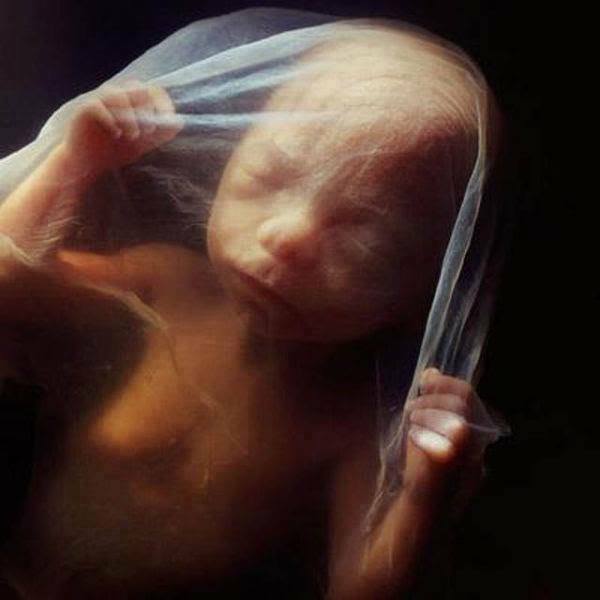

19. 到了第20周,胎兒差不多有20公分長,而且頭上也長出了胎毛。

20.懷孕24週,雙手舉在臉前的小寶寶真的太萌了~

21.懷孕26週,寶寶再過不久以後,就要誕生在這個世界上了。